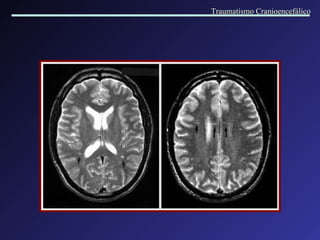

Lesão Axonal Difusa A lesão axonal difusa é mais frequentemente observada nas interfaces de tecidos com diferentes densidades. Os locais de acometimento mais comuns são: região cortico-subcortical nas regiões frontal e t emporal , corpo caloso,  fornix,  tronco cerebral, núcleos da base,  c á psul a interna. A RM é muito mais sensível na detecção destas lesões. Traumatismo Cranioencefálico

Lesão Axonal Difusa Traumatismo Cranioencefálico